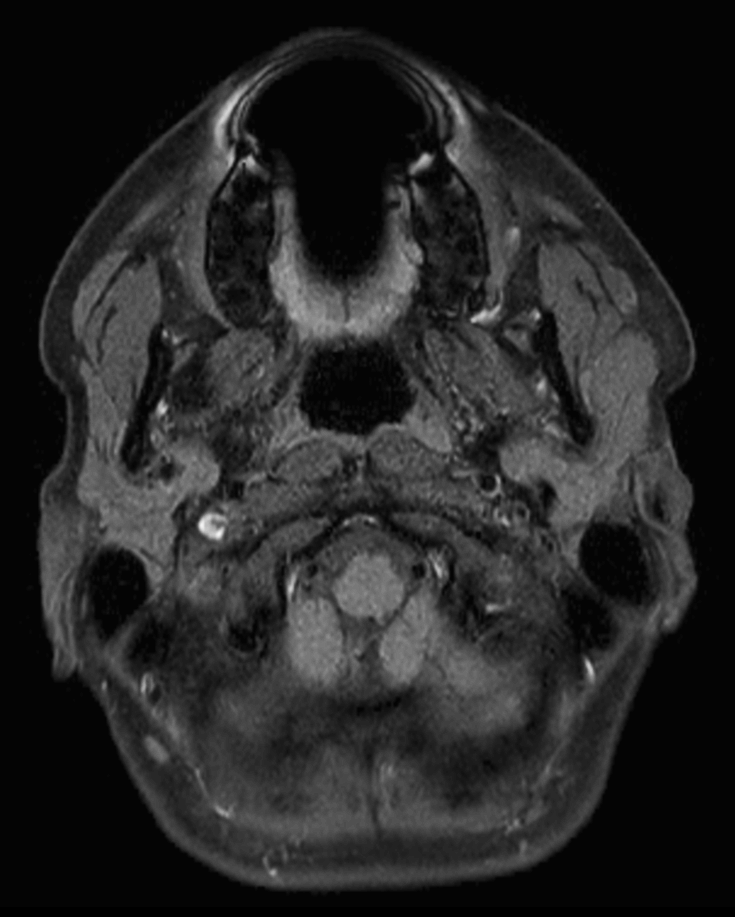

Axial T2w TSE